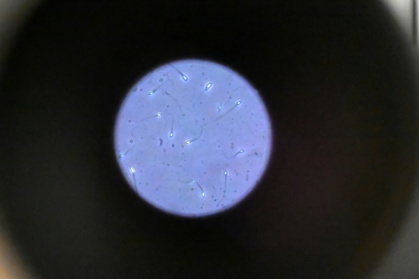

"Les centres motivaient les donneurs de sperme en leur promettant qu'ils ne seraient jamais recontactés" - Damien MEYER (AFP)